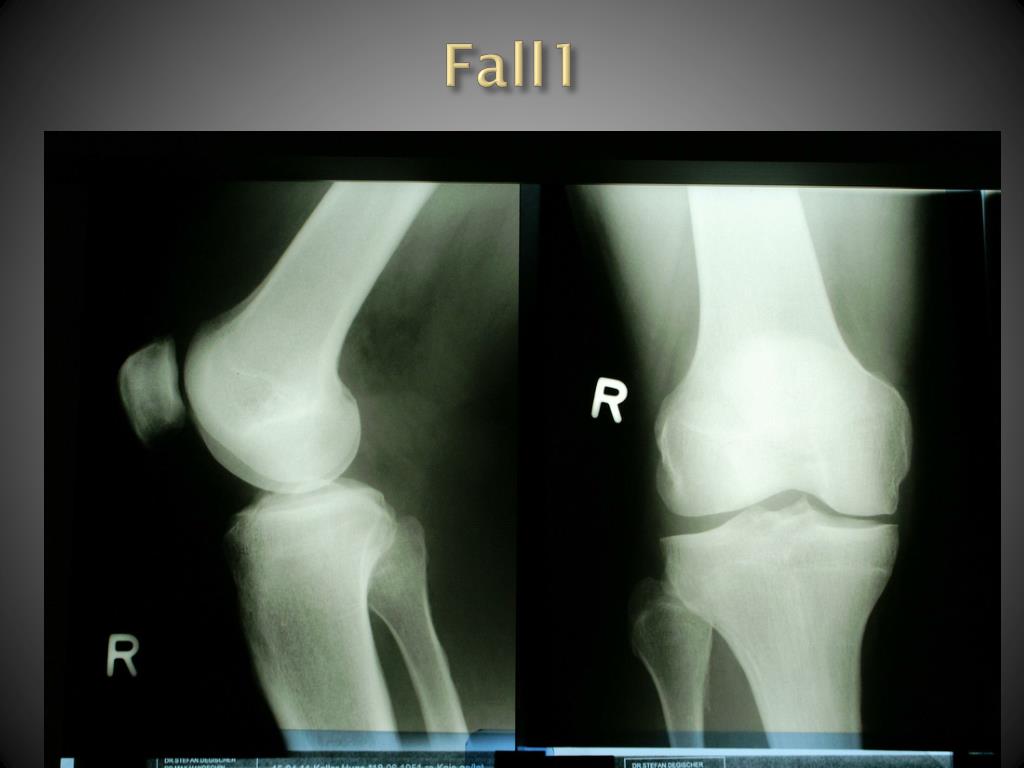

6. Fall1 Swiss Family Docs Conference 25.-26. Aug 2011

2. Fall 1 A: 60 jähriger Patient ist beim Bau einer Steinmauer ausgerutscht ( einzige mögliche Ursache, die erinnerlich ist) und hat nachher eine Schwellung des rechten Knies festgestellt, welche seit 2 Wochen nicht verschwunden ist. Er spürt ein Druckgefühl bei Belastung. Treppabsteigen spürt er stärker als treppaufsteigen. Kühlung hat gut getan. Swiss Family Docs Conference 25.-26. Aug 2011

4. Fall 1 Klinik: Das rechte Knie ist geschwollen, geschätzte Ergussmenge ca 40- 60 ml, das Knie ist leicht überwärmt. DD über dem med. Gelenkspalt, aber auch proximal davon und parapatellär, med. stärker als lateral. Kein Rotationsschmerz, kein Hyperflexions- oder Hyperextensionsschmerz. Bei Flex/Ext.: Leichtes Knacken parapatellär. Keine mediale Aufklappbarkeit und schmerzfreie Abd./ Add. Swiss Family Docs Conference 25.-26. Aug 2011

5. Fall1 Was tun wir? Wollt ihr noch etwas zur Anamnese/ Klinik wissen? Weiter abklären? Wie, wann, warum? Swiss Family Docs Conference 25.-26. Aug 2011